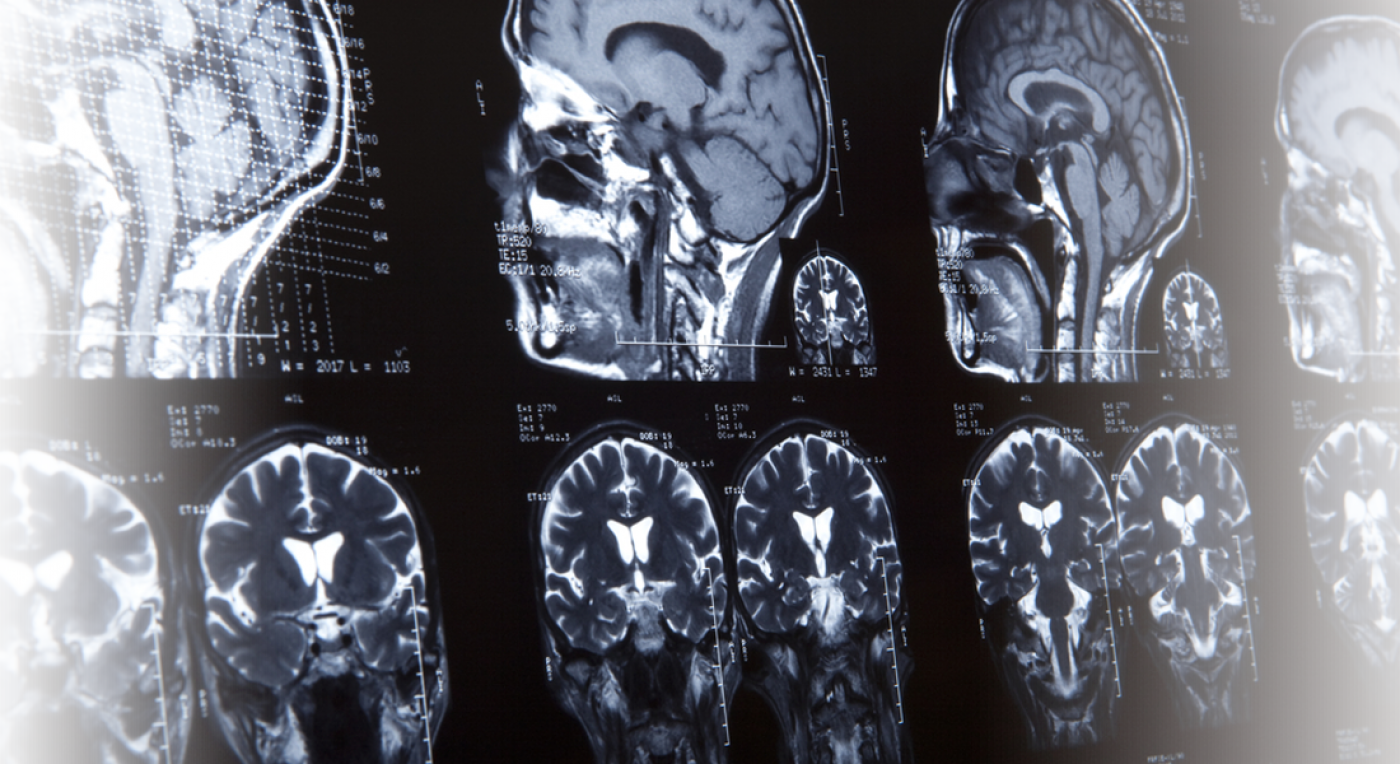

You may have the right to seek compensation for your medical bills, loss of income, and pain and suffering. One of the most serious types of brain injuries is a traumatic brain injury, or tbi. Dallas traumatic brain injury lawyer we can help you with your concussion or head injury caused by a car accident.

The rotation and disruption of the brain inside the skull will sever or shear the brain’s long connecting nerve fibers. Our brain injury attorneys are familiar with texas law, and we know the court system. Call the reyes browne reilley law firm today.